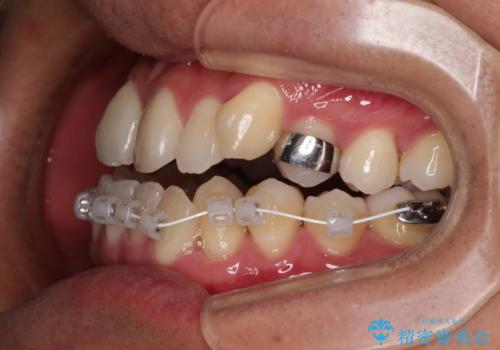

- 矯正装置

- 審美装置

- 上下前歯部のデコボコを主訴として来院された患者様です。

上顎の歯列弓が下顎に対して狭いため、臼歯のかみ合わせがが咬頭対咬頭の状態です。

上顎の急速拡大装置を使用して、上顎骨を側方に拡大することで上顎歯列弓を拡大し、それに伴い下顎歯列弓も拡大できるようにして、歯列を整えていくこととしました。